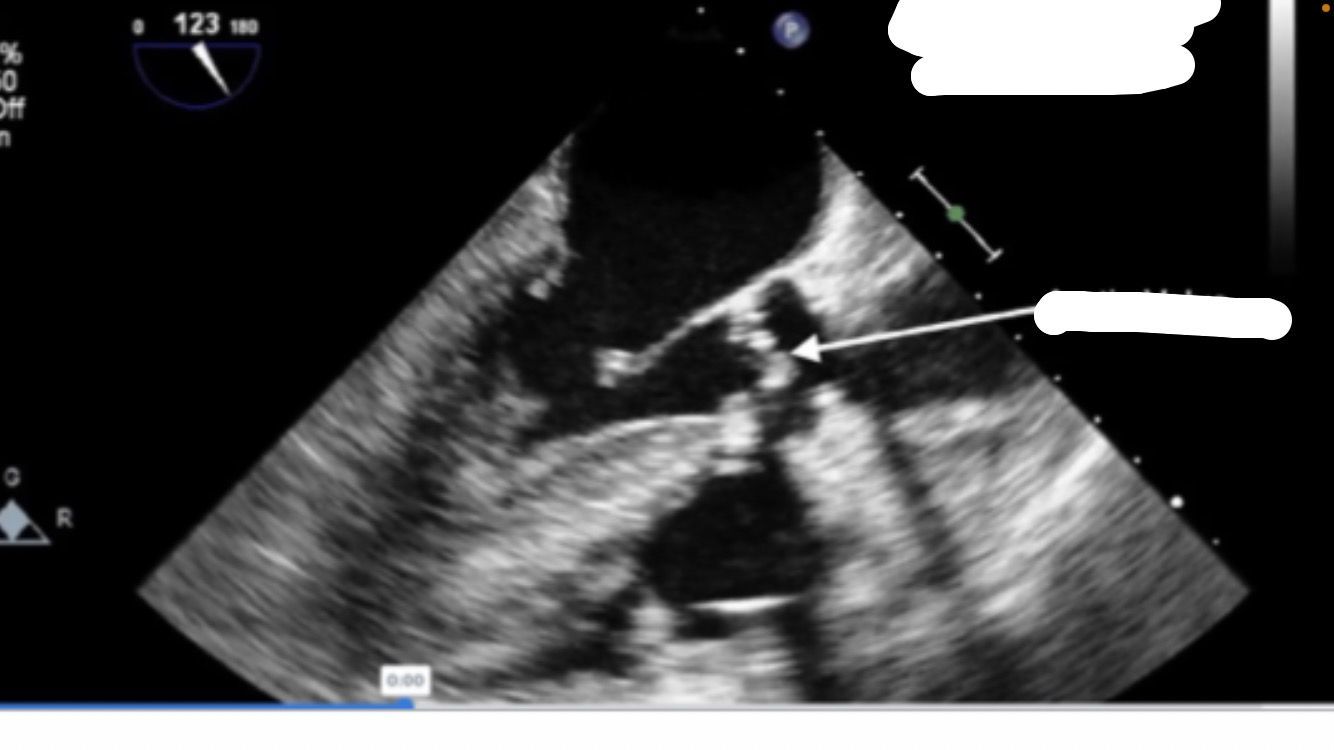

Mid-esophageal ascending aortic LAX

Mid-esophageal Long Axis view. LAX